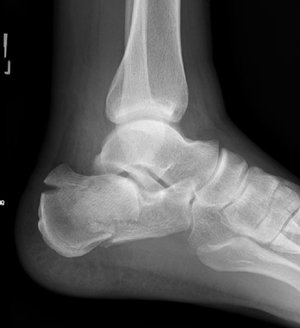

TOTAL ANKLE REPLACEMENT :: ORIF CALCANEUS :: ORIF ANKLE FRACTURE DISLOCATION :: COMPLEX BUNION AND LESSER TOE CORRECTION :: TALUS FRACTURE -1 :: TALUS FRACTURE -2 :: LISFRANC REPAIR :: COMPLEX TRIPLE ARTHRODESIS 1 :: COMPLEX TRIPLE ARTHRODESIS 2 :: MINIMALLY INVASIVE BUNION REPAIR 1 :: MINIMALLY INVASIVE BUNION REPAIR 2 :: ARTHROSCOPIC CARTILAGE REPAIR :: TENEX SPUR DEBRIDEMENT :: Haglunds Debridement and Achilles Repair